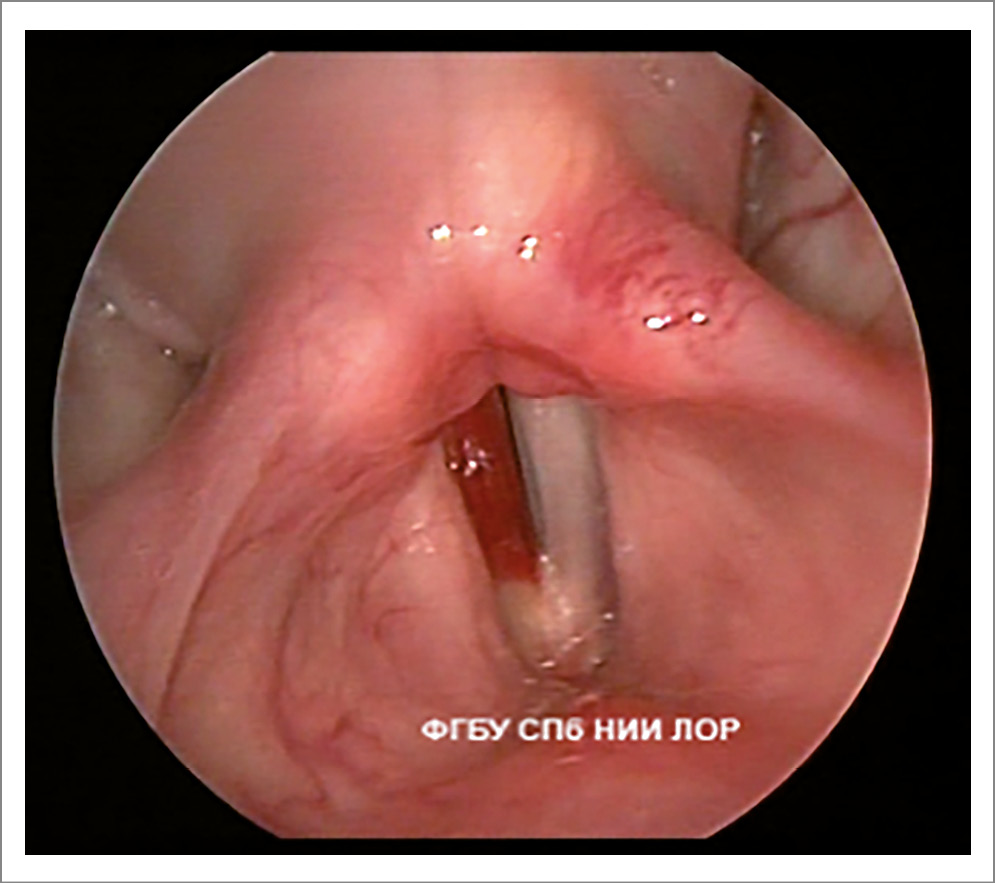

- Недостаточное натяжение медиального края голосовой складки во время вдоха обусловлено снижением тонуса голосовой (m. vocalis) и щитоперстневидной (m. anticus) мышц. Край выглядит несколько вогнутым (рис. 3).

- Симптом «зияния гортанных желудочков» характеризуется максимальным отведением вестибулярных складок при вдохе, что позволяет увидеть гортанные желудочки; следует отметить, что в здоровой гортани гортанные желудочки необозримы.

Рис. 3. Функциональная дисфония по гипотонусному типу (вдох): зияние гортанных желудочков, недостаточное натяжение медиального края голосовых складок.